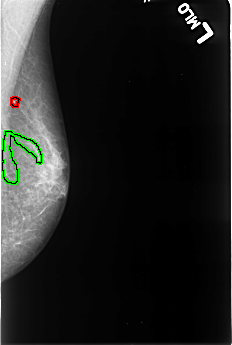

B_3246_1.LEFT_MLO

FILE: B_3246_1.LEFT_MLO.OVERLAY

TOTAL_ABNORMALITIES 2

ABNORMALITY 1

LESION_TYPE CALCIFICATION TYPE SKIN DISTRIBUTION N/A

ASSESSMENT 2

SUBTLETY 4

PATHOLOGY BENIGN_WITHOUT_CALLBACK

TOTAL_OUTLINES 1

BOUNDARY

ABNORMALITY 2

LESION_TYPE CALCIFICATION TYPE VASCULAR DISTRIBUTION N/A